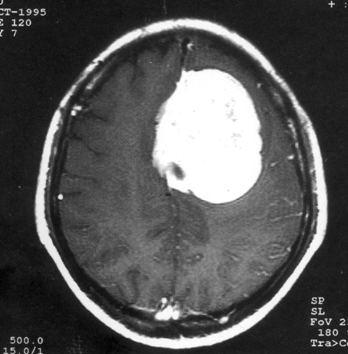

问题 病历摘要:??患者女性,37岁。大便时突起炸裂样头痛3小时,伴喷射样呕吐。既往体健。体检:T37.5℃,BP145/90mmHg,R20次/分,P85次/分。神志清楚,颅神经检查无异常,颈强直,克、布氏征(-),四肢肌力、肌张力正常,病理征(-)。 目前治疗颅内动脉瘤的主要方法有哪些?

选项 A.r刀 B.开颅动脉瘤夹闭术 C.开颅载瘤动脉夹闭及动脉瘤孤立术 D.开颅动脉瘤包裹术 E.血管内动脉瘤栓塞术 F.X刀 G.动脉瘤颈结扎术 H.颈动脉结扎术

答案 BCDE